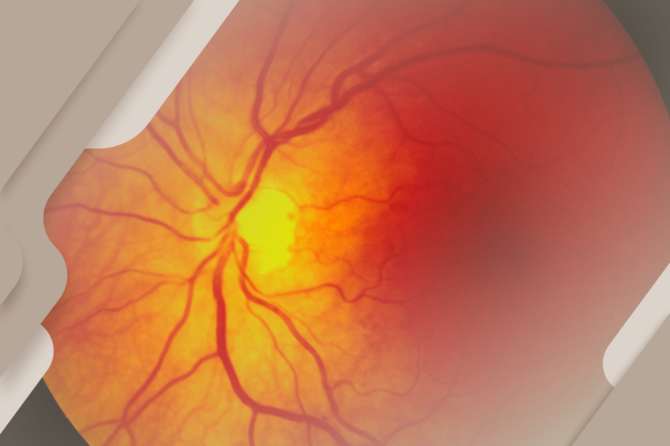

Você sabia que a retina é a tela da nossa visão?

A retina é a estrutura no fundo do olho responsável por captar a luz e transformá-la em sinais que o cérebro interpreta como imagens. Por isso, cuidar da saúde da retina é essencial para manter uma visão clara e saudável.

A retina é uma fina camada de tecido localizada no fundo do olho e tem uma função essencial para a visão. Ela funciona como uma espécie de “tela”, responsável por captar a luz que entra pelos olhos e transformá-la em sinais que serão enviados ao cérebro.

Quando a luz atravessa estruturas como a córnea e o cristalino, ela chega até a retina. Ali, células especializadas chamadas de fotorreceptores convertem essa luz em impulsos elétricos. Esses sinais são então transmitidos ao cérebro pelo nervo óptico, onde a imagem é interpretada e reconhecida.

Qualquer alteração na retina pode comprometer seriamente a visão. Doenças como descolamento de retina, retinopatia diabética e degeneração macular podem afetar essa estrutura e prejudicar a qualidade da visão. Por isso, consultas regulares com o oftalmologista são fundamentais para a prevenção e o diagnóstico precoce de problemas oculares.

Cuidar da saúde dos olhos é essencial para manter uma boa visão ao longo da vida. Exames oftalmológicos periódicos ajudam a identificar alterações precocemente e garantem que a “tela” da nossa visão continue funcionando da melhor forma possível.